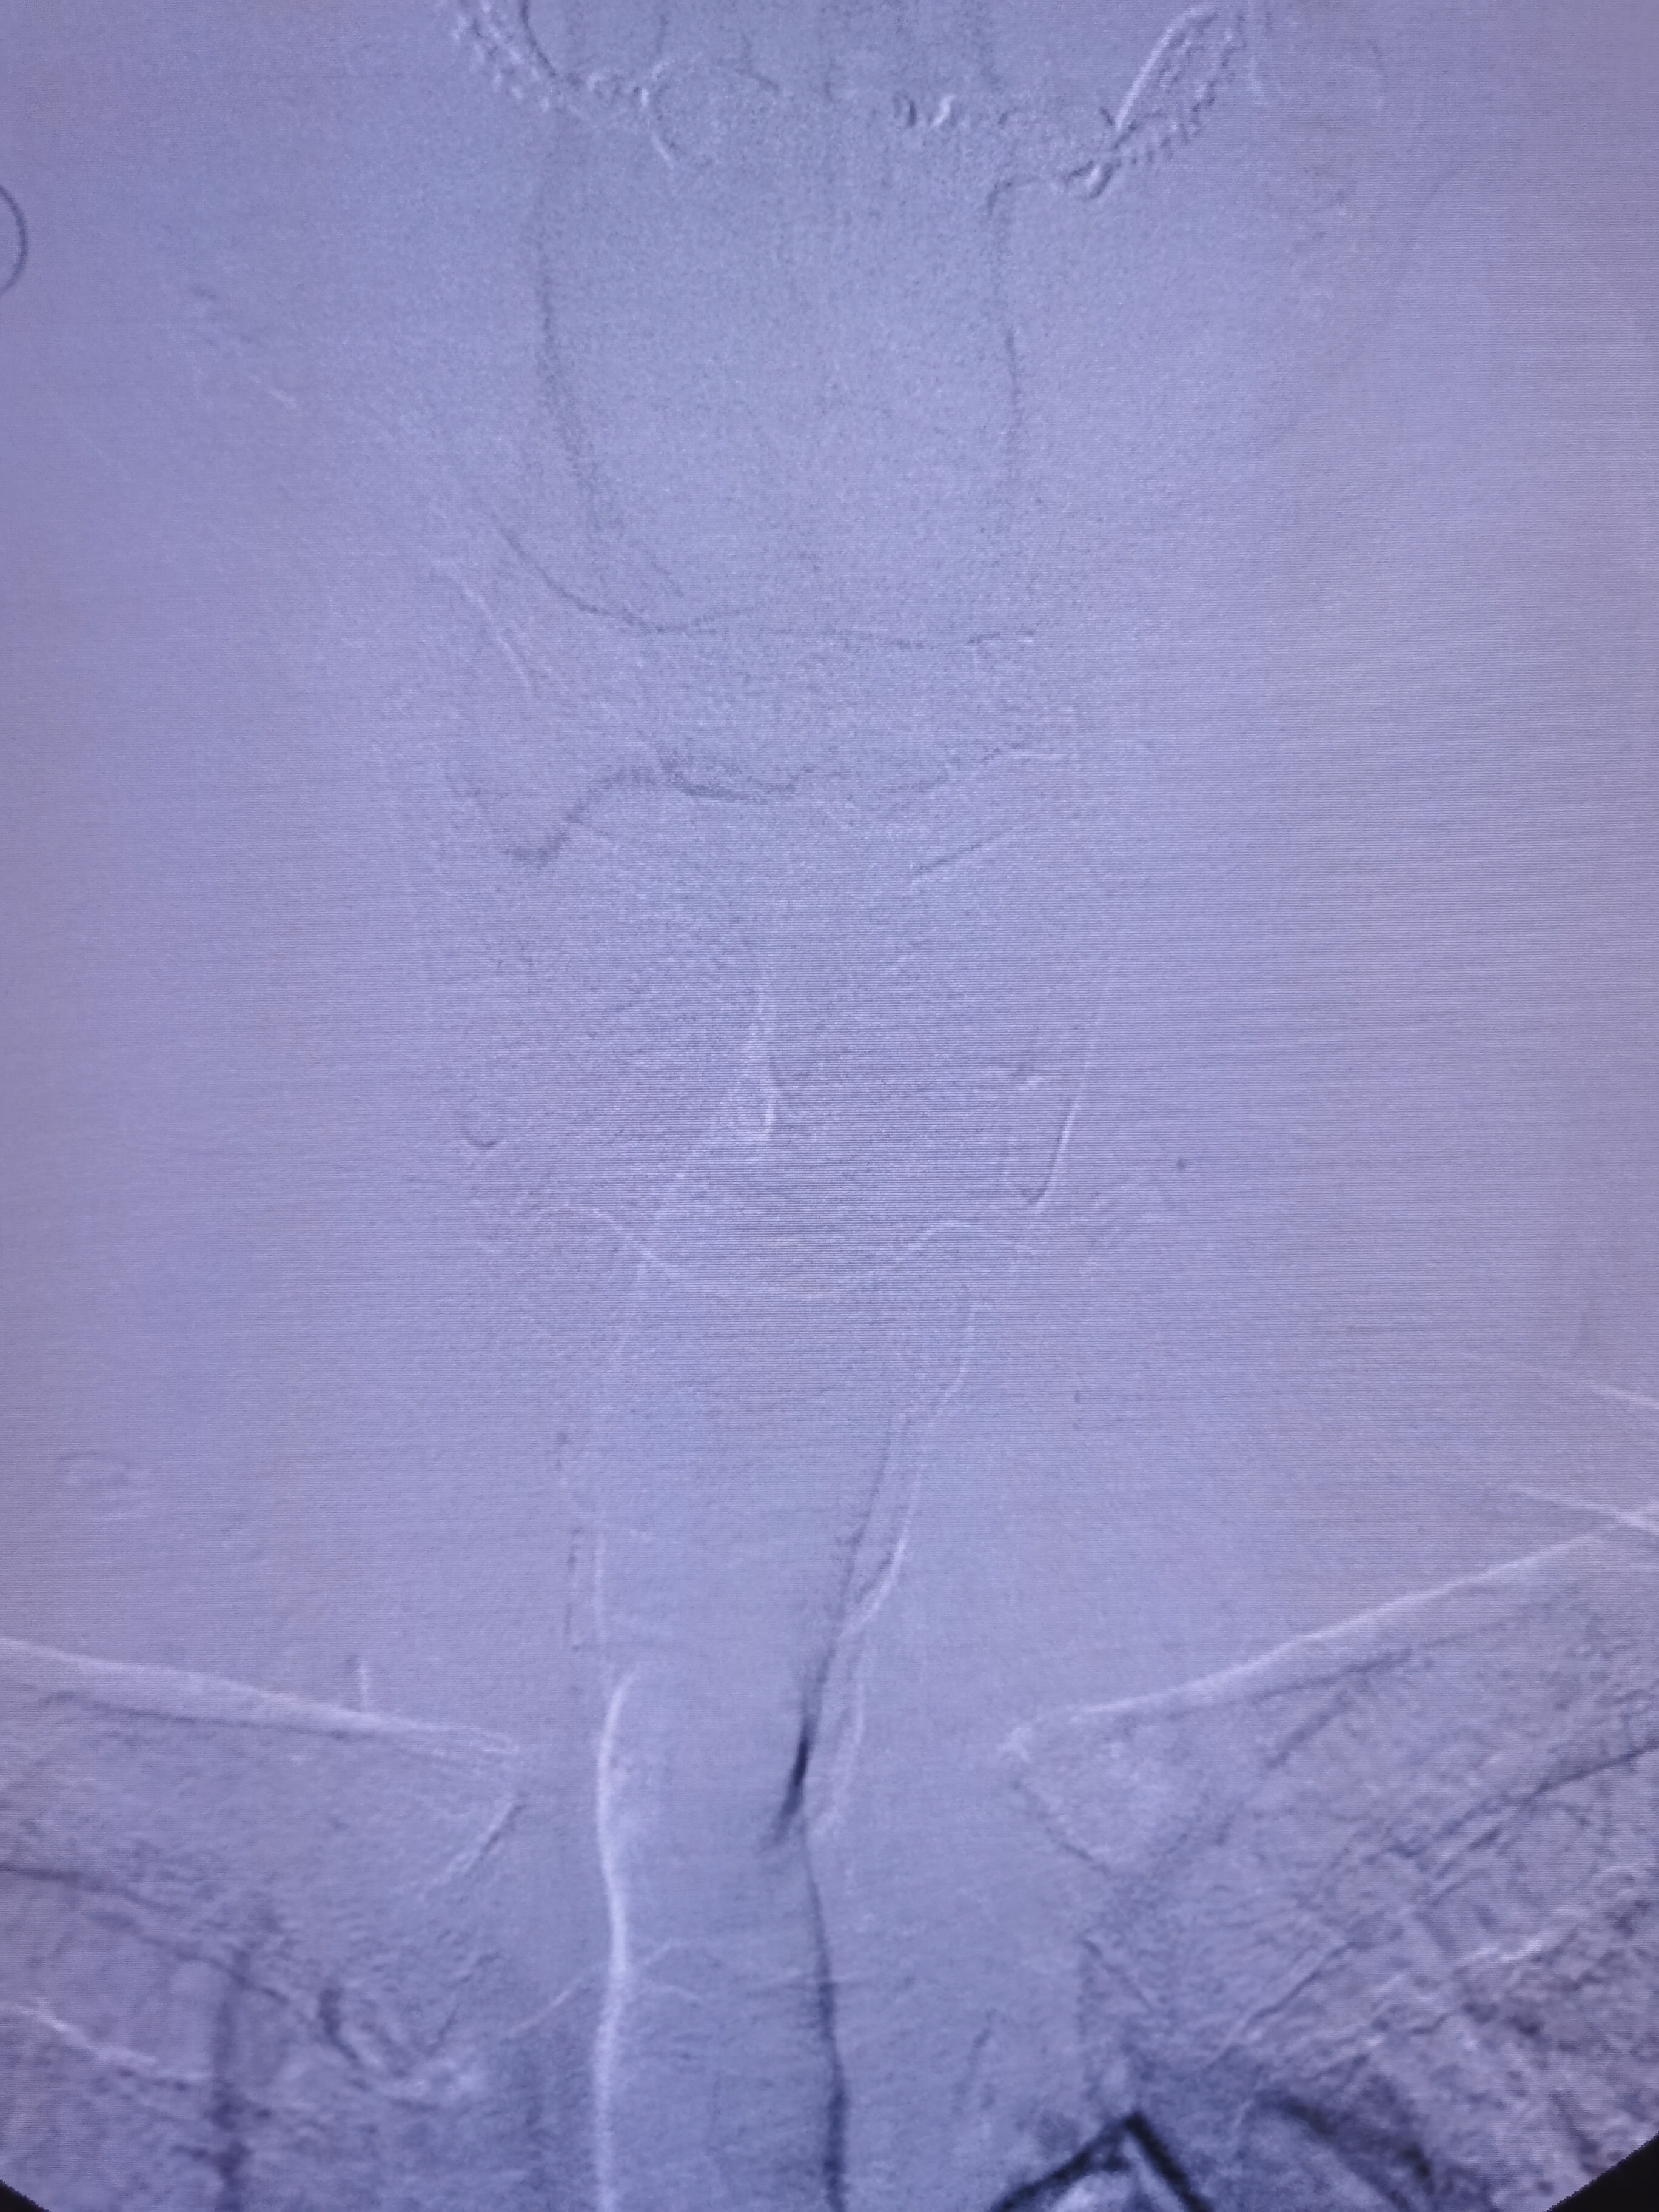

左侧锁骨下动脉起始部完全闭塞。

1、造影明确左侧锁骨下动脉起始部完全闭塞,右椎造影可见左椎返流,晚期可见圆钝的锁骨下动脉闭塞端,结合病史考虑闭塞时间较长。